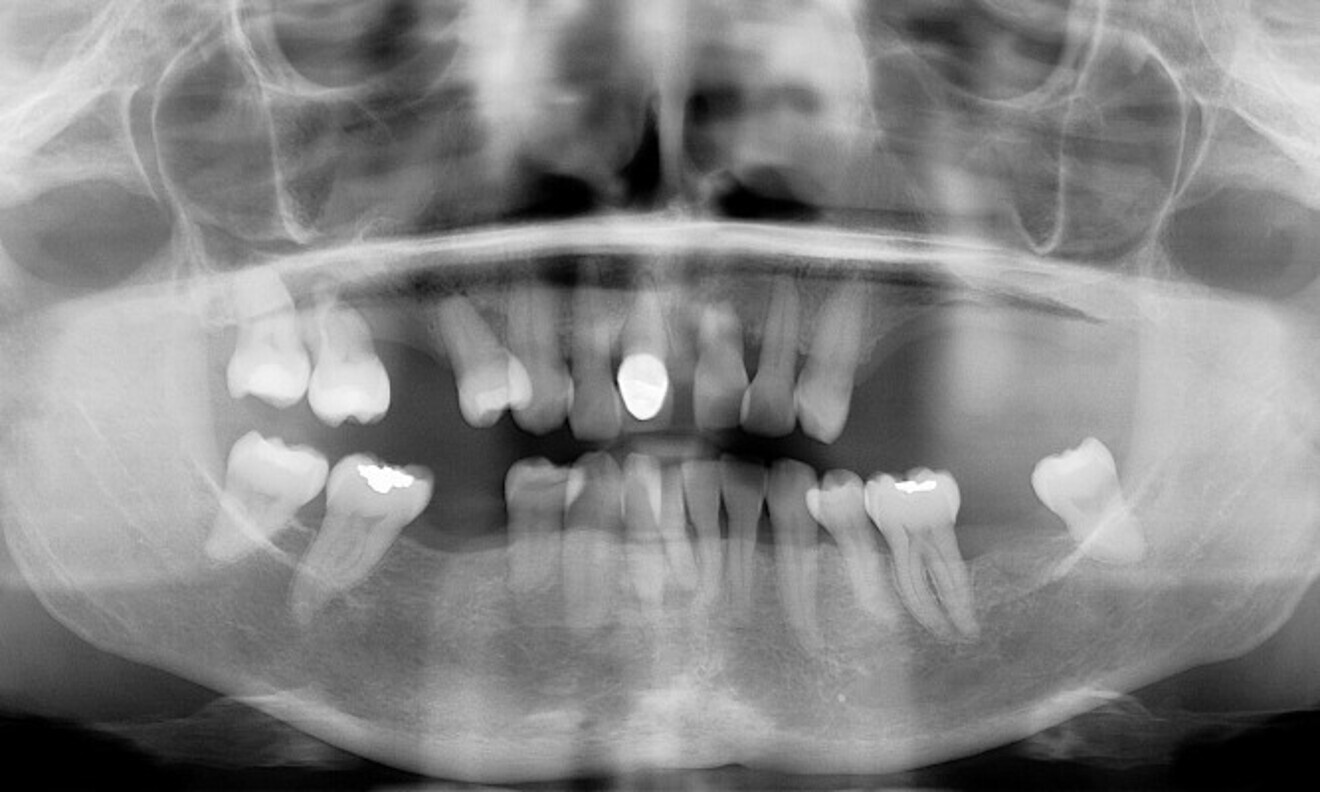

No abnormalities were found during the extra-oral examination. The patient presented with a low smile line. The intra-oral examination revealed terminal dentition due to generalised periodontal disease. The patient presented with severe resorption of the posterior maxilla bilaterally (Fig. 1). The radiographic examination showed generalised alveolar bone resorption with vertical bone defects (Fig. 2).